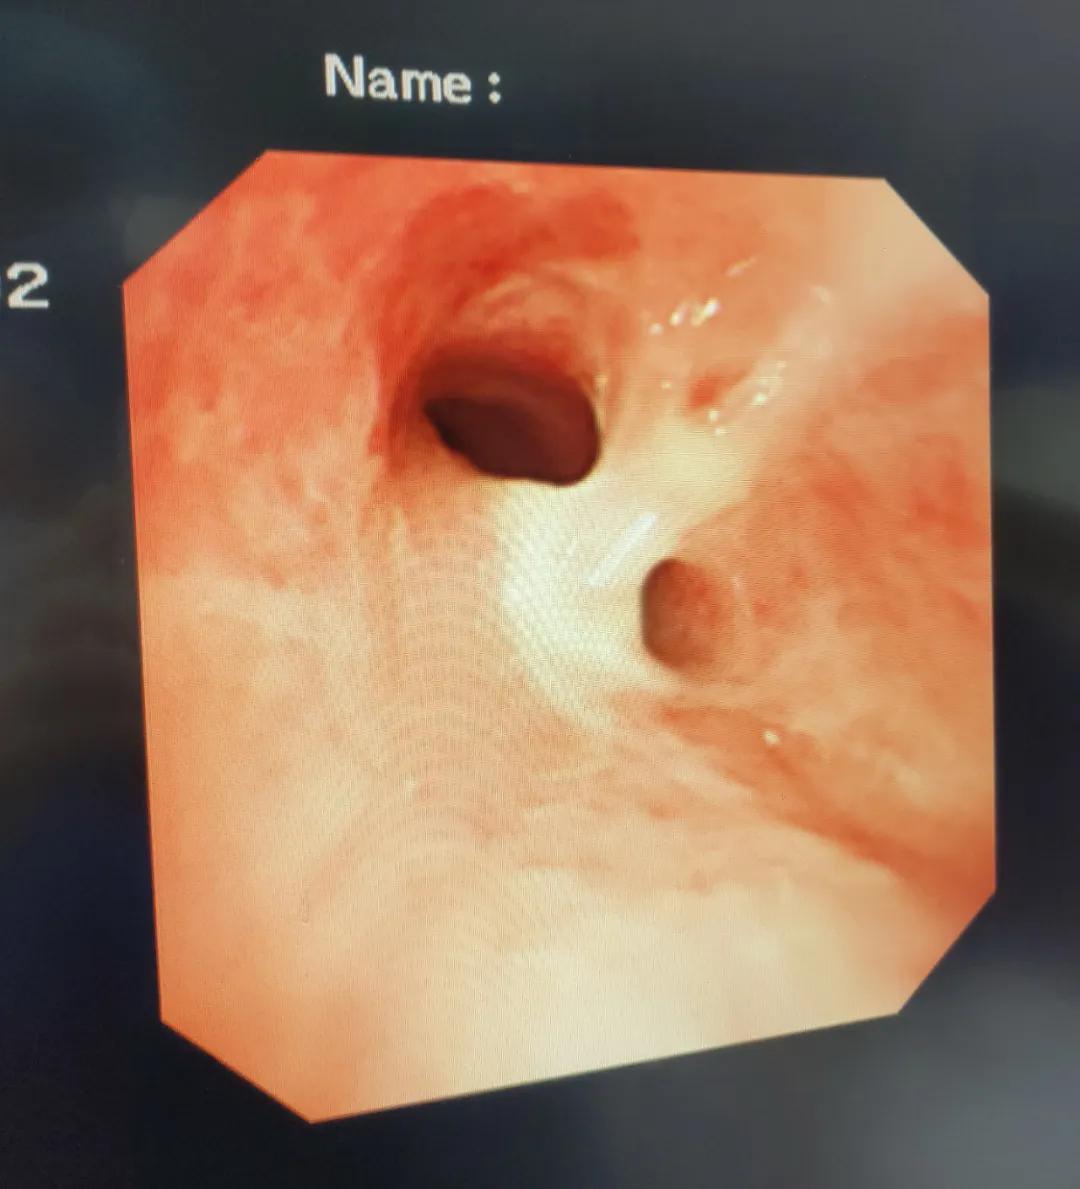

术中探查发现,食管侧已经很难看到鱼刺的头端,并且局部粘膜肿胀,形成溃疡,很容易出血。

此时的鱼刺,已化身为一把长剑,横插在了食管、纵膈、左主支气管之间,不断的咳嗽让它继续前移,情况十分危急。

左主支气管治疗前

一开始计划使用异物钳让鱼刺回退至食管,以便让它能在食道一侧暴露,但是发现效果不好,且周边肉芽组织极易出血。

在应急预案保障下,用泌碎石用的钬激光,把鱼刺从中间断开,使用异物钳分别取出两段鱼刺,完美地避免了更大的开胸手术。

左主支气管治疗后